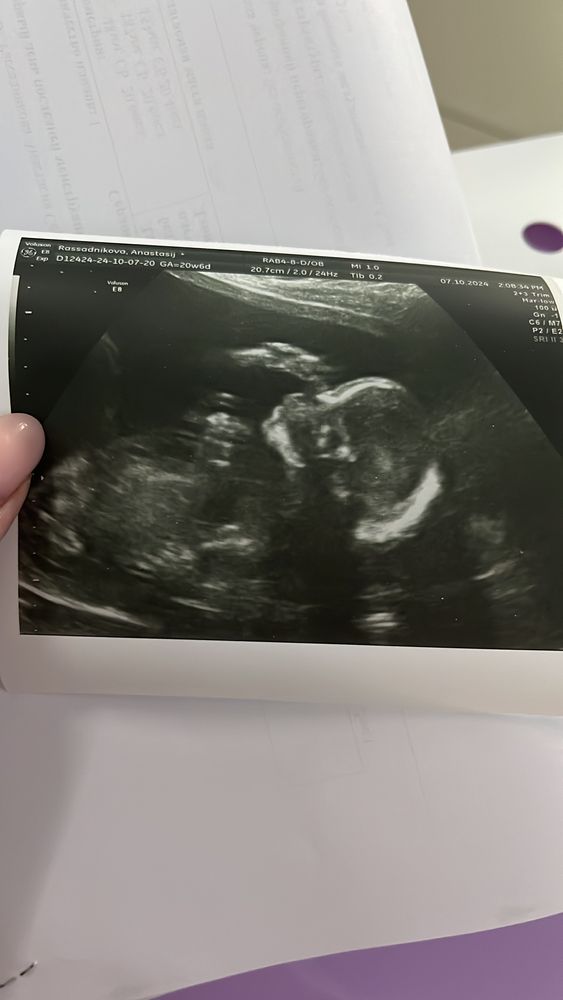

2 скрининг

Всё о нашей беременностиПривет всем. Прошли второй скрининг,с сынулей все хорошо,растет потихонечку,отставание 1 день от срока.Вечим уже 370 грамм🥹😊 Не очень критично, следующее узи через месяц,т.к. высокий риск приэклампсии. На этом узи был плохой кровоток в правой маточной артерии,теперь переживаю🤔🫣Животик растет потихонечку,иногда прям большой, а иногда и нет почти🤣Только купила штаны для беременных и то пока носить не планирую ,до беременные брюки еще как раз😊😅